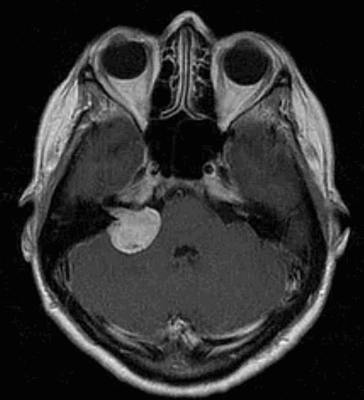

Наиболее информативным методом выявления вестибулярных шванном является МРТ головного мозга с контрастным усилением в режиме Т1 и Т2. Это исследование позволяет определить размеры опухоли, наличие перитуморозного отека, наличие признаков окклюзионной гидроцефалии, которая может быть следствием сдавления опухолью IV желудочка. Кроме этого МРТ позволяет провести дифференциальную диагностику с другими опухолями схожей локализации (чаще с менингиомой задней грани пирамиды височной кости). Еще одним стандартом диагностики является КТ в костном режиме. Независимо от снижения слуха стандартом является проведение аппаратной аудиографии.

До начала радиохирургического лечения проводится обследование, позволяющее определить точное положение опухоли и прилегающих нервных образований. Выполняется трехмерная реконструкция, отображающая детальную микрохирургическую анатомию этой области. Для этой цели с помощью МРТ получают четкую визуализацию опухоли и нервов во внутреннем слуховом проходе и области мосто-мозжечкового угла.

Если предыдущие исследования с большой долей вероятности указывают на шванному, наиболее информативным инструментальным методом визуализации считается МРТ. Это современное высокоточное неинвазивное исследование, которое позволяет определить размер и локализацию опухоли, а также увидеть состояние окружающих ее органов и тканей. Магнитно-резонансная томография проводится по назначению лечащего врача или по желанию пациента при наличии головных болей, головокружений, при подозрении на опухоль (ухудшение зрения, слуха, нарушение речи, чувствительности и движений в конечностях).

После проведения основной МР томографии может понадобиться уточняющее исследование для постановки дифференциального диагноза, уточнения размеров опухолевого процесса и степени вовлечения окружающих органов и структур. В таком случае назначается МРТ с контрастным усилением, в ходе которого в вену пациента вводится контрастное вещество. Изображения, полученные с применением контраста, дают не только точное представление о размере и границах невриномы, но позволяют оценить функциональные нарушения в органах.